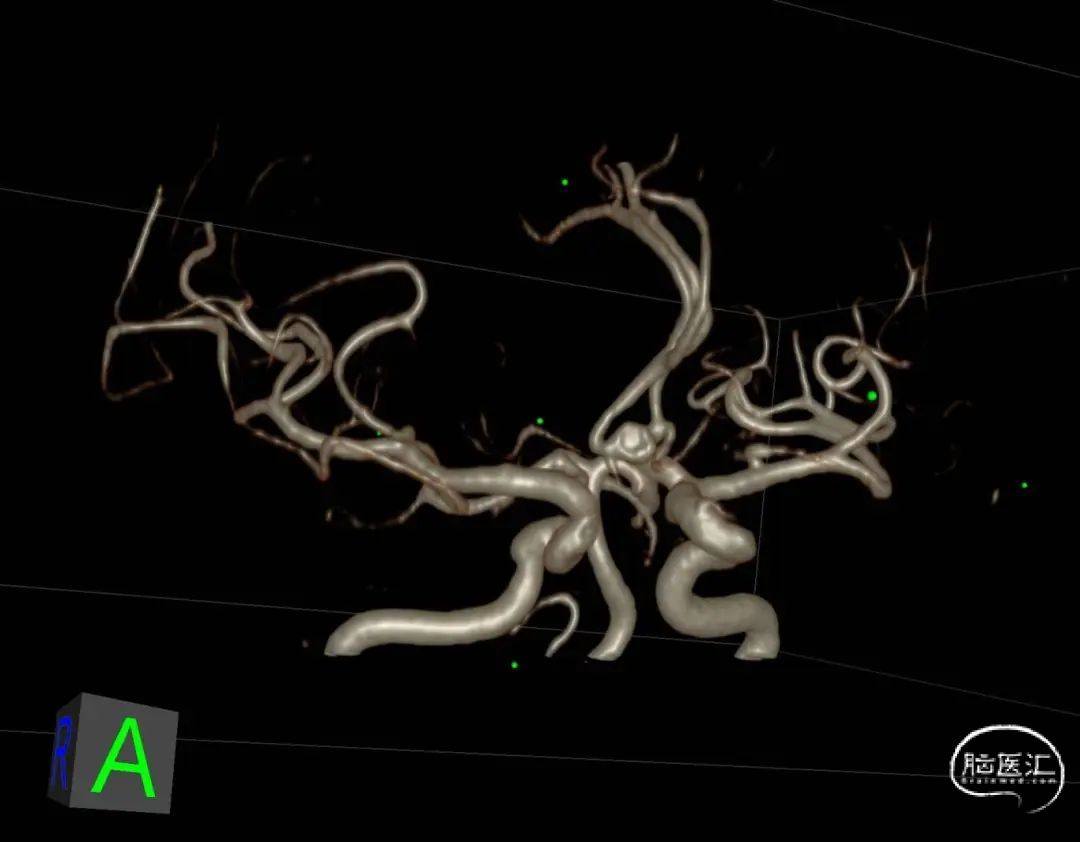

此为左侧大脑中动脉瘤,近端血管极为迂曲,瘤体有突出的子囊,动脉瘤与载瘤动脉有一定夹角,动脉瘤呈上窄下宽形状,M2段下干从瘤颈近端发出。

动脉瘤平均宽度5.41mm, 最小高度为3.71mm,瘤颈约为4.94mm,使用WEB™ SL 6*3mm瘤内扰流装置进行栓塞治疗。

右侧后交通段动脉瘤,大小约13.36mm*13.26mm,瘤体上有子囊形成,床突段至后交通段血管稍狭窄,脉络膜前动脉距瘤颈部有一定距离。

Headway 17微导管塑形后置入动脉瘤瘤体内,半释放18mm*44cm complex弹簧圈成篮,半释放3.5mm*20mm LVIS支架保护瘤颈后完全释放18mm*44cm complex弹簧圈成篮,后依次释放6枚弹簧圈栓塞动脉瘤,最后一枚弹簧圈释放完成后造影,后交通动脉瘤少量造影剂进入,完全释放支架,右侧后交通动脉瘤瘤体内极少量造影剂进入,子囊不显影,Raymond分级3级,同时造影见各主干级分支血管显影良好,遂退出系统。